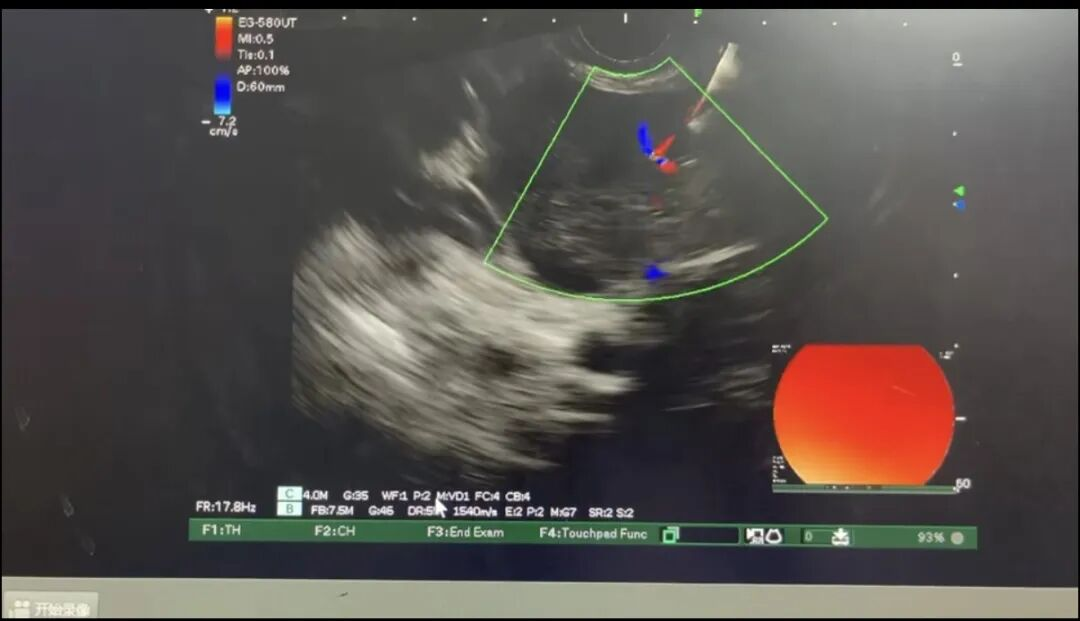

但是胰腺癌因位置深、周围结构复杂,传统手段获取病理组织难度大、风险高,诊断向来棘手。基于安全性更高的考虑,选择将病人转至消化内科开展超声内镜引导下的细针穿刺术为其获取病理组织。该技术可在超声实时监控下精准避开血管和重要脏器,穿刺路径更短、创伤更小、并发症风险更低,既能精准提取组织细胞进行病理检查,又最大程度保障了患者的安全。